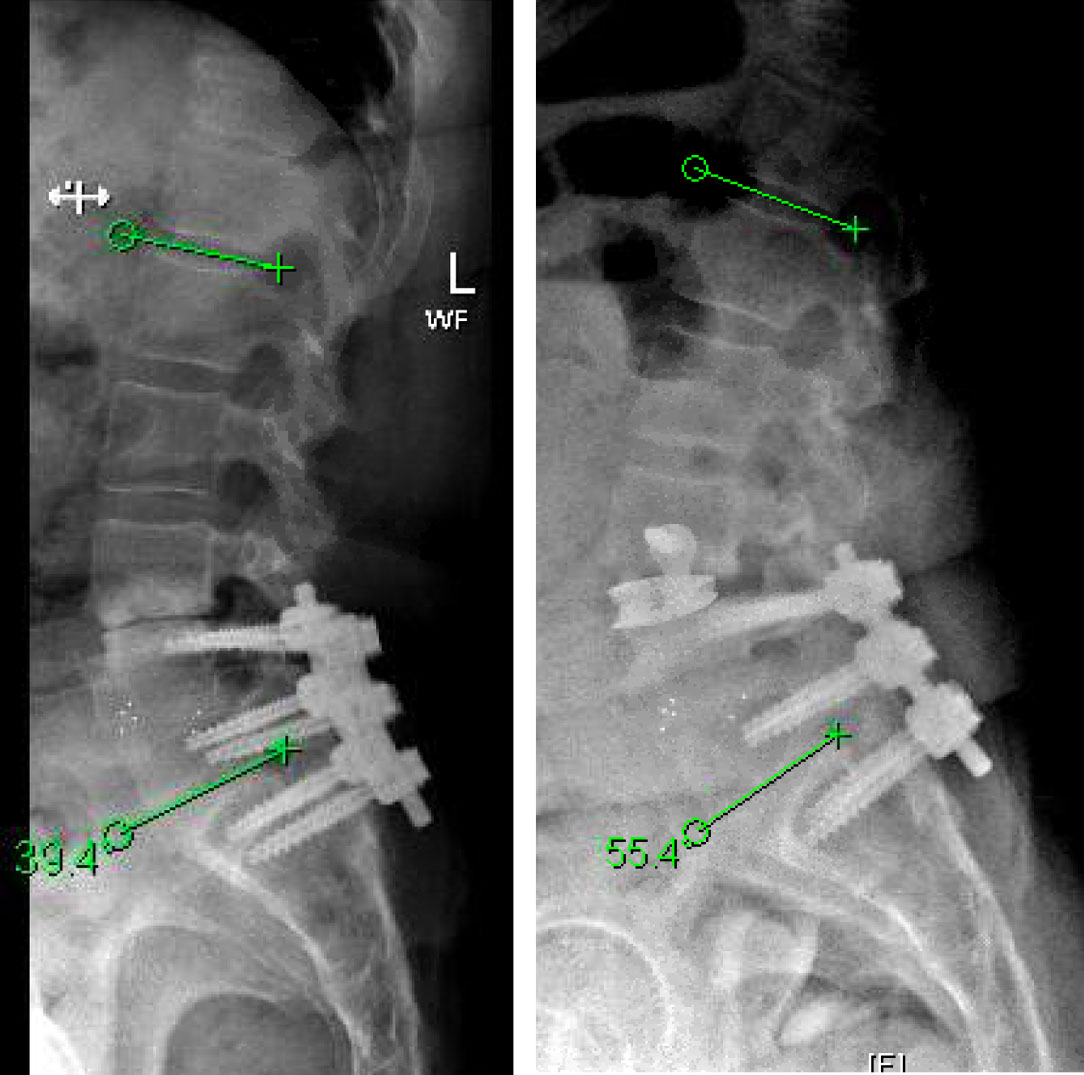

This is a 55 year-old-female who presented with progressively worsening axial low back pain and left lower extremity radiculopathy. She had a previous L4 to S1 posterior laminectomy with interbody fusion by another spine surgeon about three years prior. Imaging demonstrated L3-4 adjacent segment degeneration with spinal instability and stenosis. She additionally developed subsidence from her initial surgery, which resulted in loss of physiologic lordosis and presumptively accelerated the adjacent degenerative process. Her L4-S1 construct otherwise appeared to have a solid arthrodesis. Symptoms were debilitating and she had failed best medical management, therefore surgery was offered.

The goals of surgery were to achieve spinal stability, neural decompression, and re-establish a physiologic sagittal alignment. She had co-morbidities that precluded a more conventional open posterior approach with hardware revision. We therefore elected to perform an L3-4 Minimally Invasive Direct Lateral Interbody Fusion with Plate. This allowed for stability through the interbody device and lateral plate, indirect neural decompression by distracting the spinal canal and neuroforamina, and increase lordosis by lengthening the anterior aspect of the spine with placement of a hyperlordotic cage.